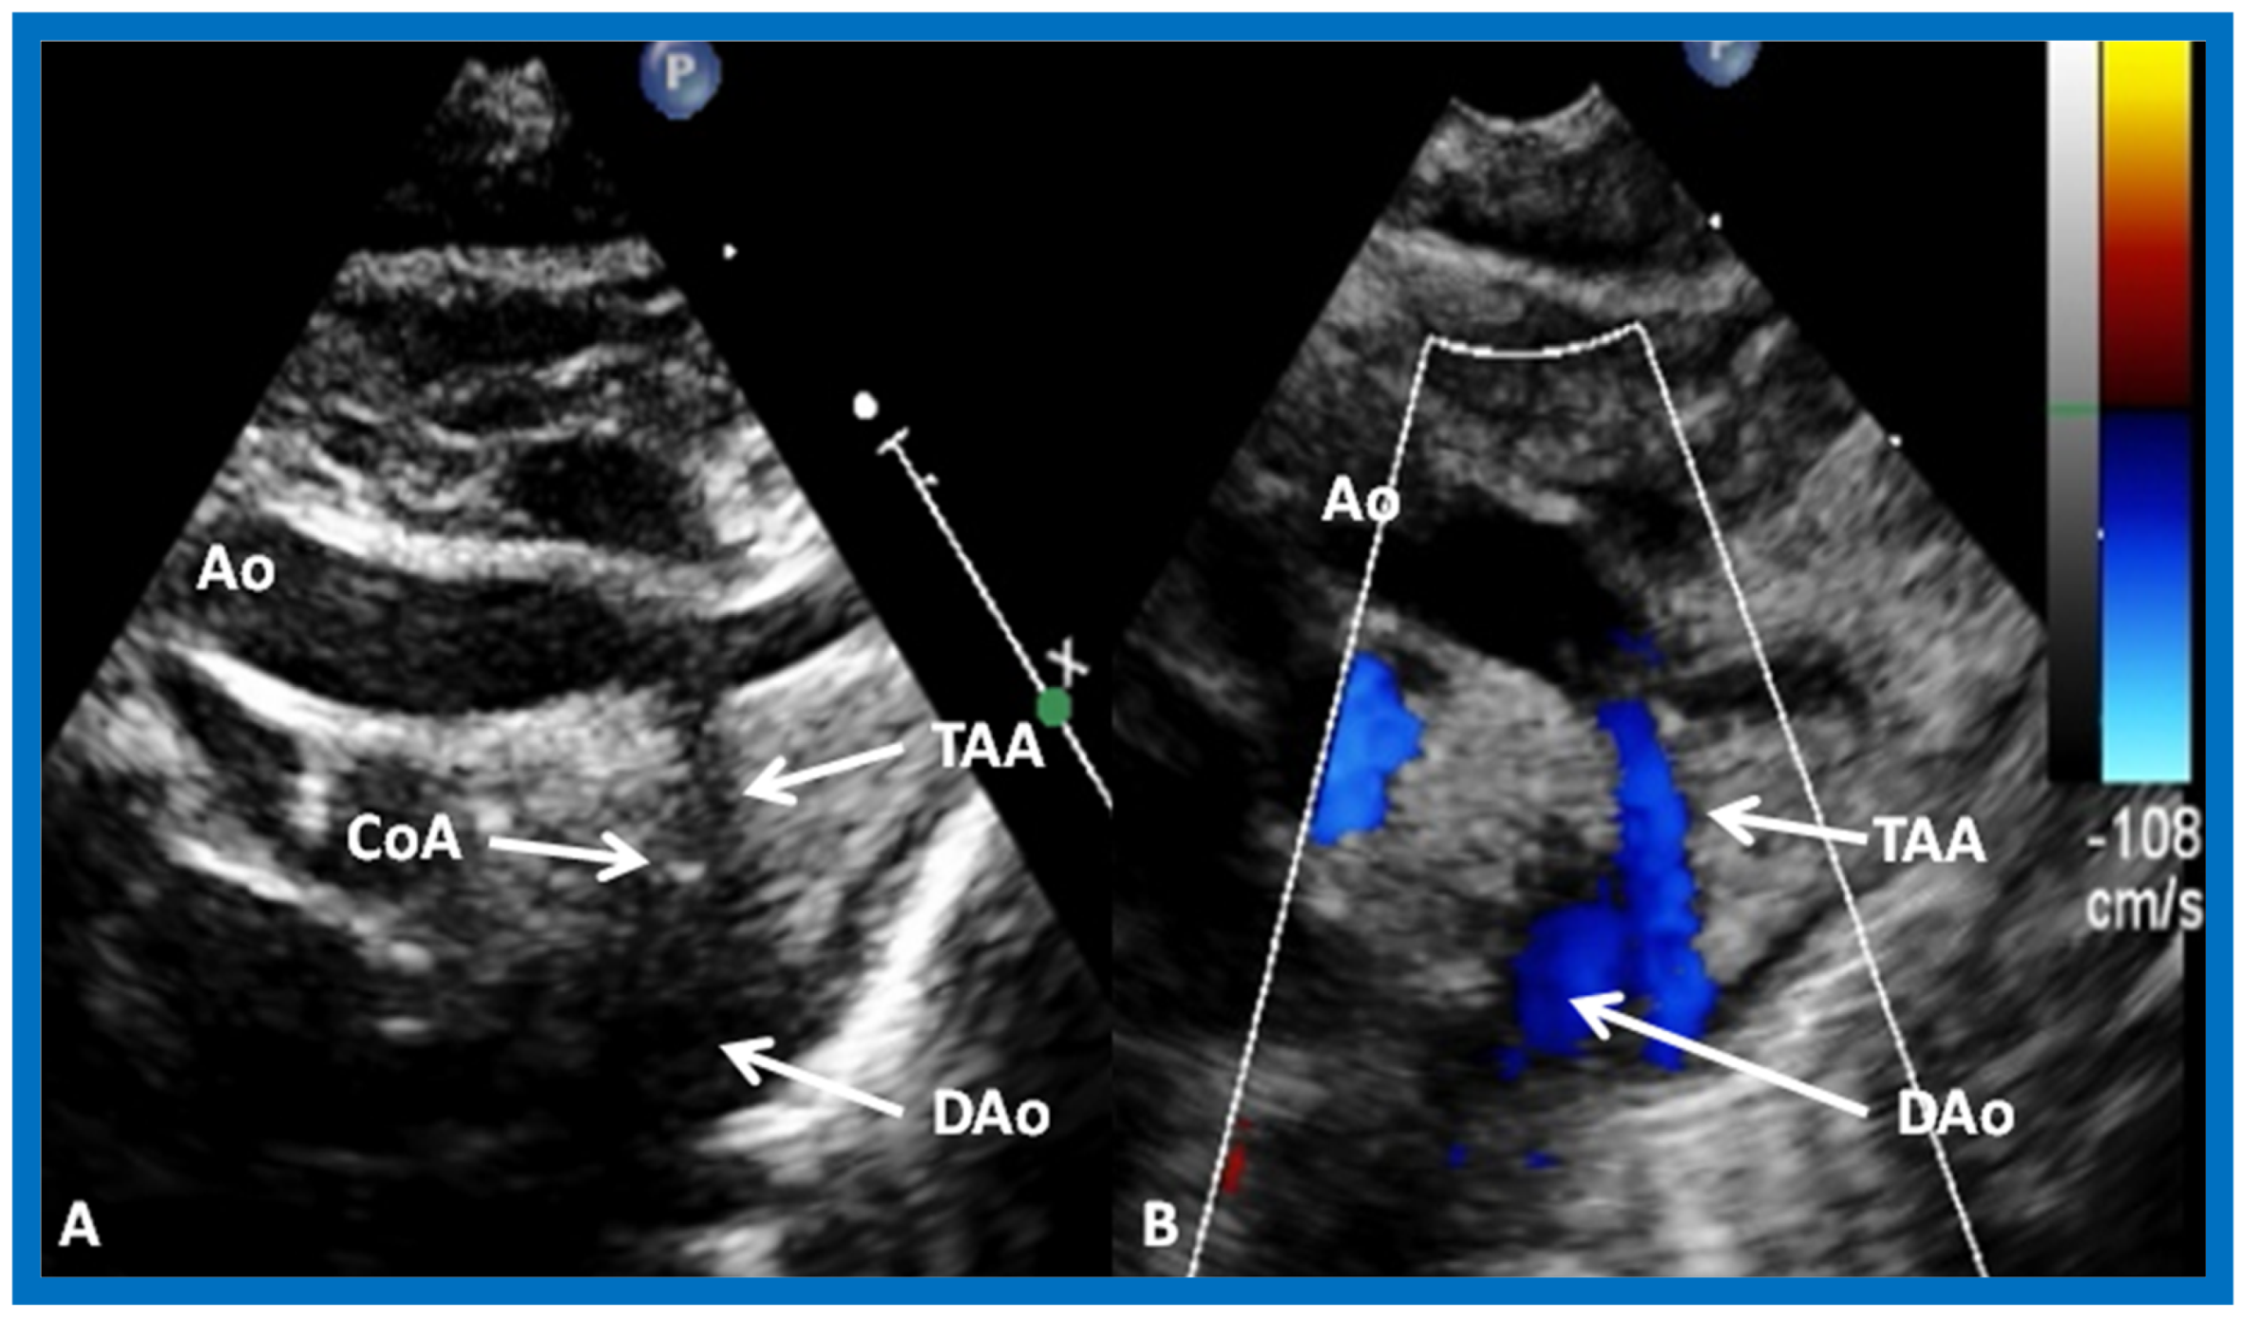

Figure 26.

Selected video frames from suprasternal notch views of the aortic (Ao) arch in 2D (A) and color flow (B) images of a neonate with tricuspid atresia and transposition of the great arteries demonstrating coarctation of the aorta (CoA) and hypoplastic transverse aortic arch (TAA). The association of CoA with tricuspid atresia plus transposition of the great arteries is well known. DAo, descending aorta. Reproduced from Rao P.S. [39].